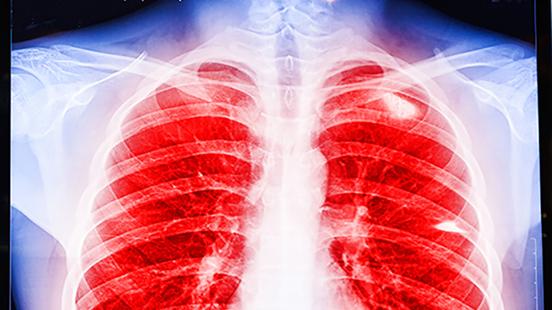

La operación se ha hecho en la parte inferior del esternón mediante una incisión de ocho centímetros, justo por encima del diafragma. Así, por primera vez no ha habido que hacer una gran abertura separando las costillas y abriendo el tórax, sistema que hasta ahora era la única opción disponible. Esta operación pionera se ha aplicado a un hombre de 65 años con fibrosis pulmonar. En Catalunya, este tipo de intervención se desarrolla de forma exclusiva en el Hospital Universitario Vall d'Hebron tanto para niños como para adultos. Desde el inicio del programa, a Vall d'Hebron se han realizado más de 1.500 trasplantes pulmonares.

Los cirujanos hicieron manualmente una incisión de ocho centímetros en la piel por debajo de la xifoides y por encima del diafragma, y en el agujero abierto colocaron un separador de partes blandas, un sencillo utensilio de plástico que permite mantener la incisión abierta y limpia durante la operación para sacar y meter los pulmones. A partir de aquí, la operación fue 100% robótica: se introdujeron cuatro brazos del robot Da Vinci por cuatro orificios de 8 a 12 milímetros de ancho para desarrollar la operación. El robot Da Vinci permite un trabajo de gran precisión, ya que ofrece una amplia visibilidad y más grados de libertad en los movimientos. Se pueden realizar incisiones mínimas, menos invasivas y precisas, y elimina el temblor o los movimientos involuntarios de los cirujanos y las cirujanas y también el cansancio postural en las intervenciones largas.